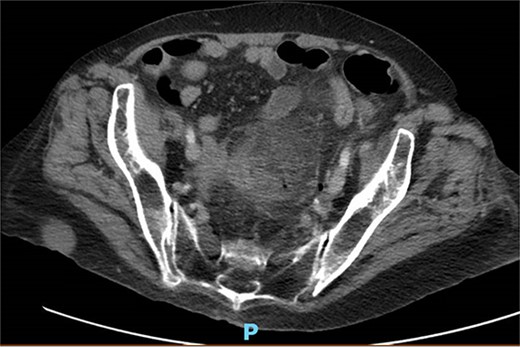

A 65-year-old female with a history of hyperlipidemia, hypertension, hip replacement, lumbar spinal fusion, chronic pain management, and prior laparotomy for endometriosis presented with a 3-day history of nausea, vomiting, and abdominal pain. She had no prior history of diverticulosis or colonoscopy. On examination, she was afebrile and hemodynamically stable. Physical examination revealed left lower quadrant tenderness, swelling, erythema, and fluctuance, suggesting an abdominal wall abscess (Figs 1 and 2). Laboratory tests showed leukocytosis with a count of 24.6 and a positive urinalysis with 2+ leukocytes. A CT scan of the abdomen and pelvis revealed a 3.8 × 3.6 cm air and fluid pocket in the low left anterior abdominal wall, indicative of an abscess likely at the site of a previous drain (Fig. 3). Additionally, there was a 2.8 × 1.8 cm irregular air pocket in the left pelvis, where an abscess had been identified in prior imaging.

CT from readmission with anterior abdominal wall abscess and left pelvic abscess.